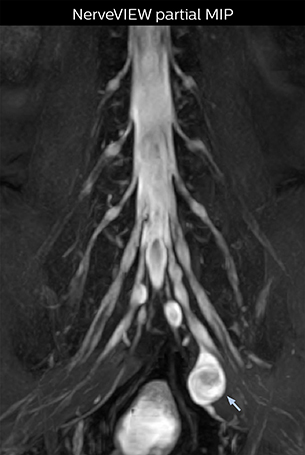

The key concept in MR neurography, Dr. Yabuki stresses, is the ability to directly visualize spinal nerves, versus inferring the presence of pathology indirectly. “Before NerveVIEW, we estimated compression of the nerve by looking for the presence or absence of fat signal on other MR images,” he says.

“For example, in sagittal images, when the presence of fat is observed in the intervertebral foramen, it suggests that there is a margin around the nerve. Similarly, the absence of fat indicates that the nerve is being compressed. So, we used to deduce nerve compression indirectly. With NerveVIEW, however, we can observe the condition of the nerves directly, regardless of the presence or absence of fat. We always prefer such direct observation of anatomy over having to make an inference about it.”

“Although symptoms of typical disc herniation and atypical hernia are very similar, the actual site of herniation is different. It is therefore important to characterize the nerve’s condition both inside and outside of the intervertebral foramina. “Conversely, if we see no abnormality in NerveVIEW, we can assume at least that there is no severe condition that requires surgery. Like this, it can help us avoid unnecessary surgery. NerveVIEW can have a tremendous impact in this way.”

“NerveVIEW is really useful for those cases where a nerve disorder is strongly suspected based on the clinical examination but our regular MRI images do not show any findings. These atypical herniations and spinal canal stenosis, occurring in 5% to 15% of the total lumbar herniation/stenosis cases are our main target when using NerveVIEW,” says Dr. Yabuki.

“The intra-luminal signal of veins, especially around the intervertebral space, can be suppressed well with NerveVIEW. As a result, we can easily observe the detailed nerve structure around the posterior ganglion,” he says. “This is why we use 3D NerveVIEW for intraforaminal stenosis and extraforaminal stenosis/herniation (lateral disc herniation). On the other hand, if herniation is suspected to exist inside the dorsal root ganglion (DRG), balanced TFE or ProSet-FFE is applied. NerveVIEW is not suitable for evaluating the median type of herniation.” The SE-EPI DWI-based method for MR neurography works well for large FOV exams like whole-body MRI, but focal examination of nerves is often limited by the attainable spatial resolution (both inplane and slice direction) and geometric distortion. “3D NerveVIEW achieves higher in-plane resolution – close to our other routine spine sequences – and the source images can be used instead of adding a fat-suppressed T2-weighted sequence,” Tanji says.